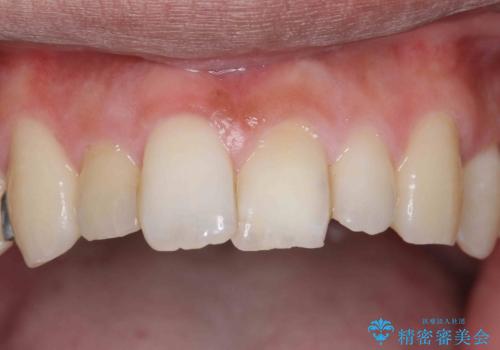

- 奥歯が虫歯になり、位置的に詰め物は難しかったため、被せものにする治療を行いました。

- 11万円 ジルコニアクラウンスタンダード10万円、仮歯1万円費用は治療当時の料金となります

頬側に咬頭が一つ多い歯であったのと、歯肉に近い位置が虫歯になっていたため、被せものでしっかり覆う治療を行いました。